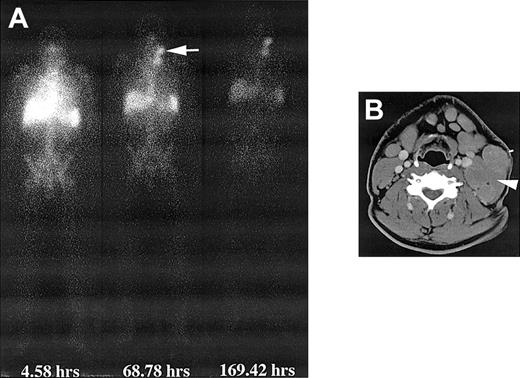

Whole-body gamma camera images showed mainly blood pool activity immediately after administration, which decreased over time but was clearly present up to 200 hours after administration (Figure 2). There was rapid uptake of 131I-labeled ch81C6 mAb in bone marrow on all patients because of the presence of tenascin-C in the extracellular matrix of bone marrow and tumor involment.25,26 Patients with large tumor masses, as shown in Figures 2 and 3, showed tumor retention of 131I-labeled ch81C6 with an effective half-life close to the physical half-life of 131I, demonstrating the long-term retention of ch81C6 mAb; however, in small masses of tumor as determined by computed tomography (CT), tumor contrast was very low because of the prolonged blood activity, and tumor retention was difficult to determine.

Whole-body and CT images after infusion of 131I-labeled chimeric 81C6 mAb. (A) Whole-body images of a patient obtained at different time points after infusion of 370 MBq 131I-labeled chimeric 81C6 mAb. Note the prolonged uptake in the nodal disease in the neck. (B) CT scan depicting the nodal disease (arrow) that accumulated the radiolabeled antibody. A biopsy sample was obtained from this node 44 hours after dosimetric infusion of 370 MBq, and the measured activity concentration was 70 kBq/g.